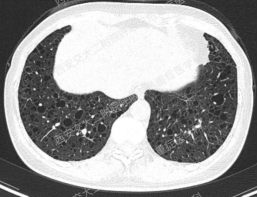

上图所示肺部囊性病变,双侧多发、大小不一,壁薄,形状不规则,呈圆形及扁平状为主,部分融合,分布多在纵隔胸膜下。入院后查血尿粪常规、肝肾功能电解质、凝血功能、血糖血脂心肌酶、BNP、肌钙蛋白正常;红细胞沉降率23mm/h,PCT、CRP正常;TB-spot阳性(阳性对照管反应水平123.49 pg/mL),TB-DNA、PPD试验、痰X-pert、痰涂片、痰培养均阴性;女性肿瘤标志物全套未见异常;结缔组织病相关指标:自身抗体ANA 1:100、CENP B阳性,CCP抗体25.1U/ml(正常参考值<17U/ml),ANCA、抗核抗体谱、体液免疫全套均阴性;血气分析大致正常,肺功能检查: FEV1占预计值78.2%,FEV1/FVC 69.55%,RV/TLC 49.62%,支气管舒张试验阴性,FeNO50 29.2ppb。

患者无吸烟史,二手烟接触不多。追问家族史,父母已故(具体不详),兄弟姐妹6人,大姐有肺大泡病史,未具体诊治,育有2子,均体健。进一步行双肾CT平扫提示双肾轻度积水,进一步行全外显子基因检测,回报FLCN突变:

该例患者BHD诊断明确,无皮肤及肾脏受累,仅表现为多发囊性肺病变。建议忌烟,避免受凉、劳累及剧烈运动,防范气胸。鉴于肺功异常,建议每年复查1次胸部CT及肺功能检查;每3年筛查1次肾脏MRI。同时建议其兄弟姐妹及其子完善症状前FLCN基因检测。